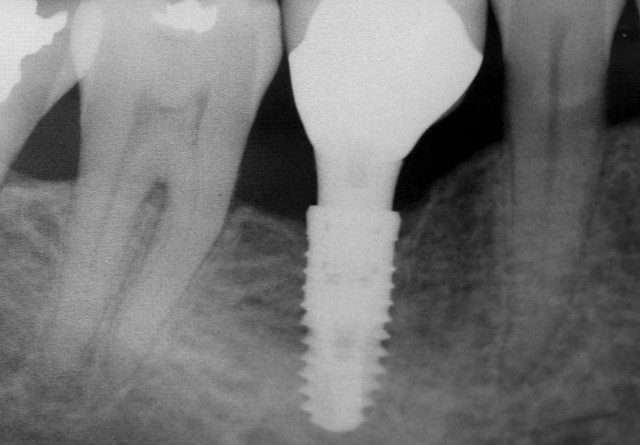

Read MoreZobni vsadek je najboljša rešitev Implantati ali zobni vsadki so praviloma najboljše nadomestilo za izgubljene zobe. To so posebne vrste

Read MoreMedicinski pripomočki pa se lahko v vsakdanjem življenju uporabljajo tudi zaradi drugih razlogov, na primer estetskih. Kljub temu tudi takšni